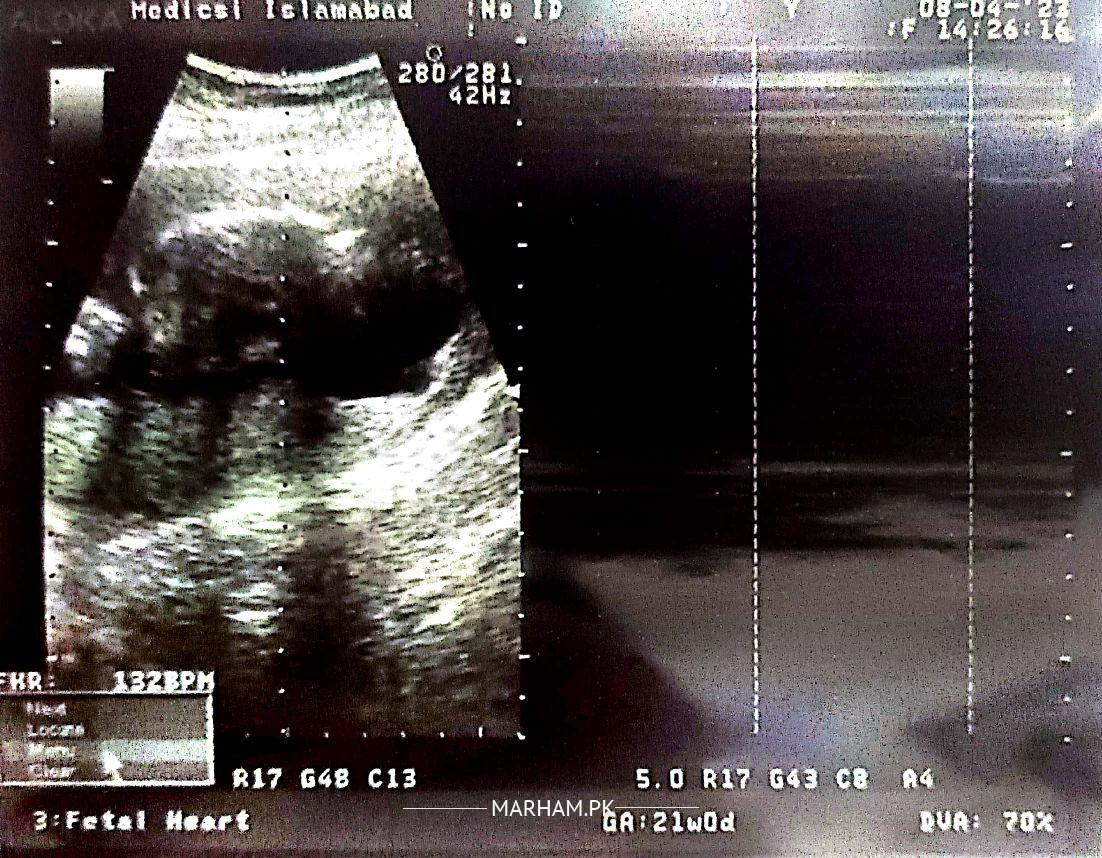

Asking For Self, Female 23, Lahore

Want to know about gender? or any guess....

no one can declare gender on seeing this scan

Not mentioned in the report

not mention